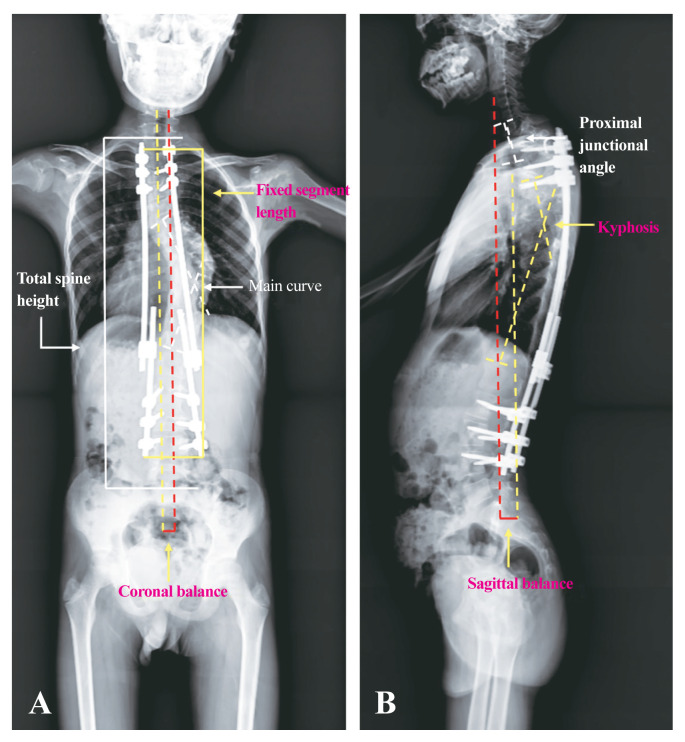

Abstract Image